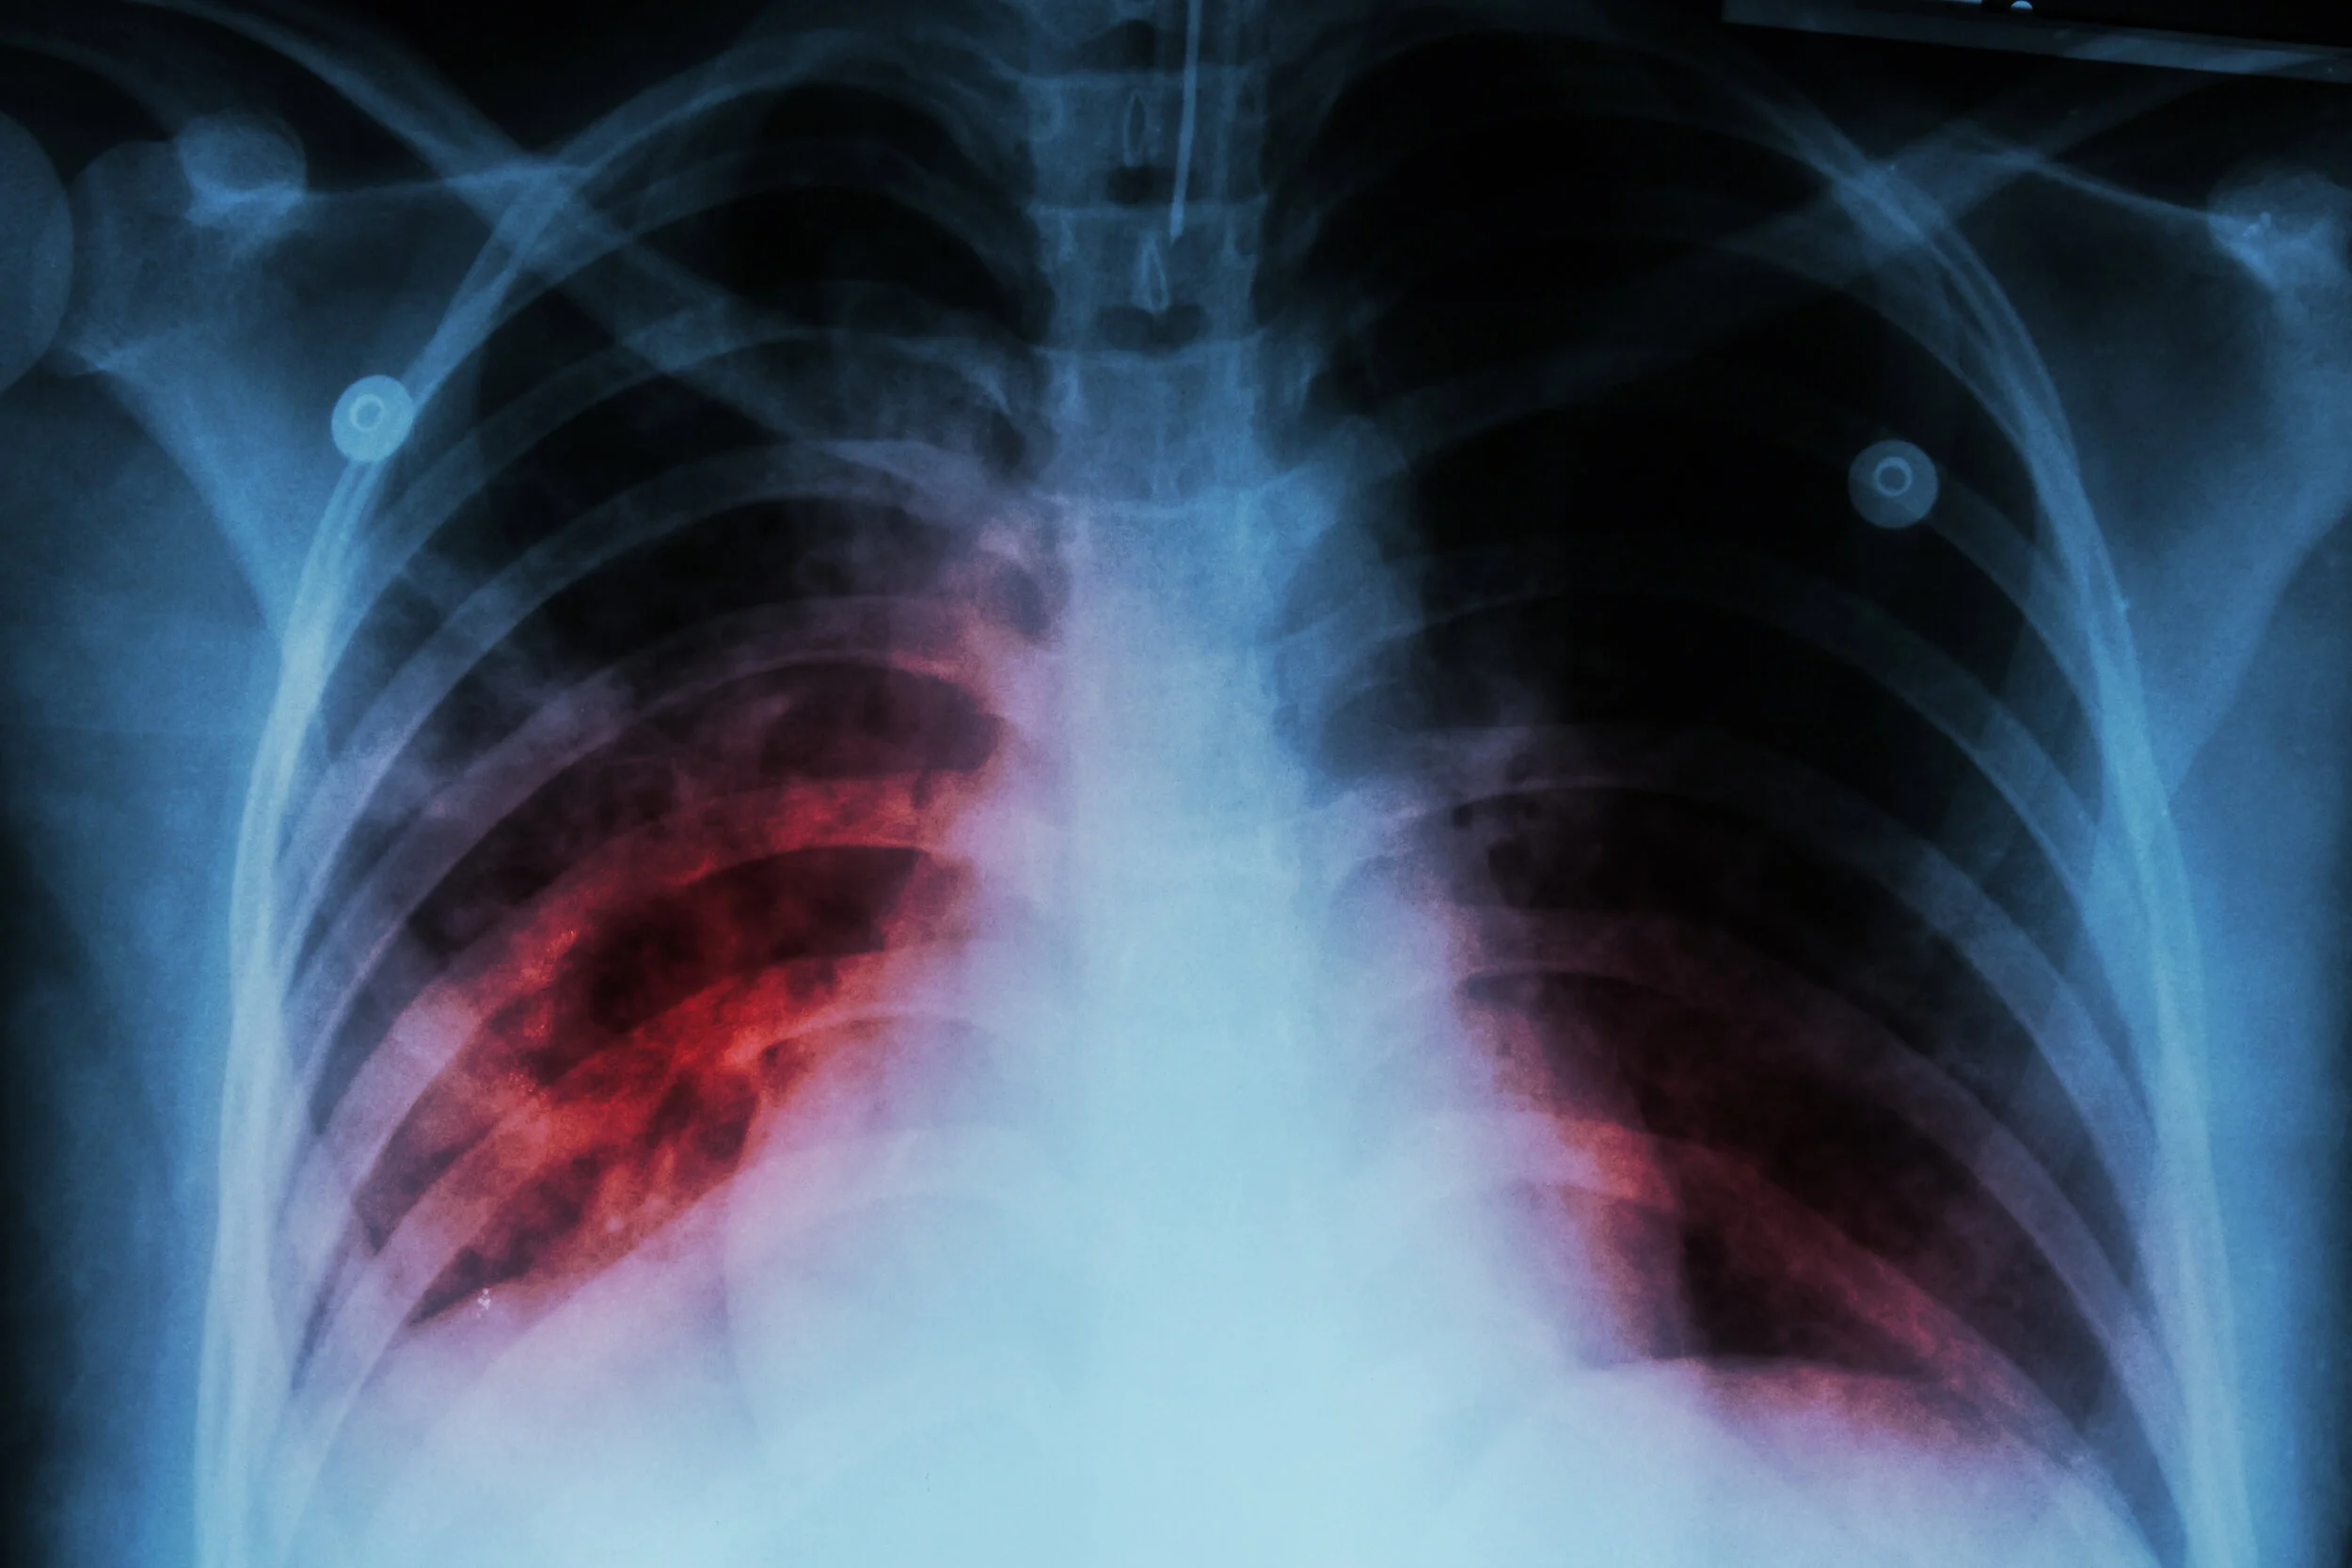

EPPA Physicians are experts in the diagnosis and treatment of disorders of the lungs and airways ranging from bronchitis and asthma to more chronic conditions such as pulmonary fibrosis and lung cancer. At EPPA, we work hard to provide fast and accurate diagnoses and the best treatment plans for your specific pulmonary needs.

With the combined expertise of our talented pulmonary specialists, we can help you treat a variety of pulmonary infections, including:

• Interstitial Lung Disease

• Pertussis (Whooping Cough)

• Allergy-induced lung disease

• Bronchiolitis

• Pneumonia

• Influenza

• Bronchiecstasis

• Deep Vein Thrombosis (DVT

• Pulmonary Fibrosis

• Tuberculosis

• Sarcoidosis

• Nontuberculosis Mycobacteria

• Severe Acute Respiratory Syndrome